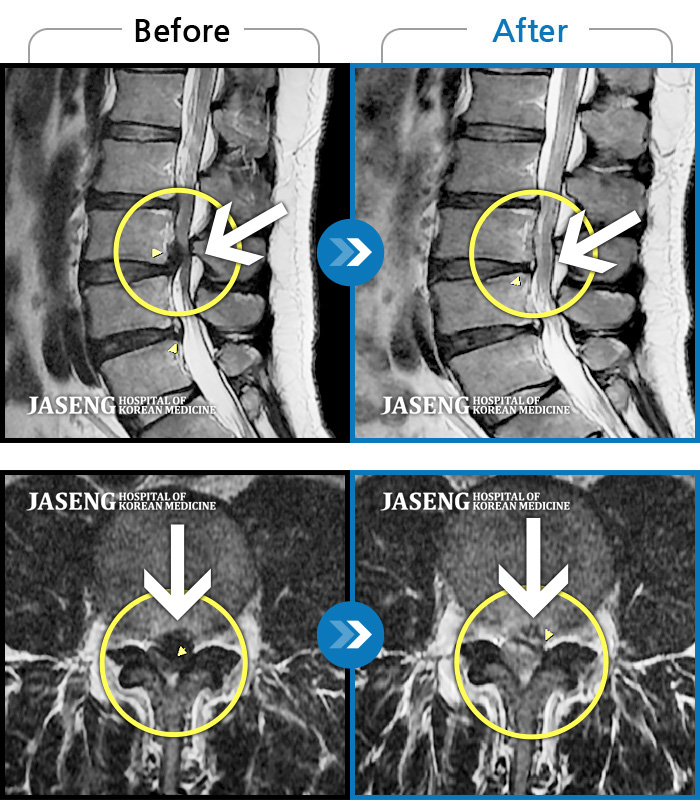

• 허리디스크